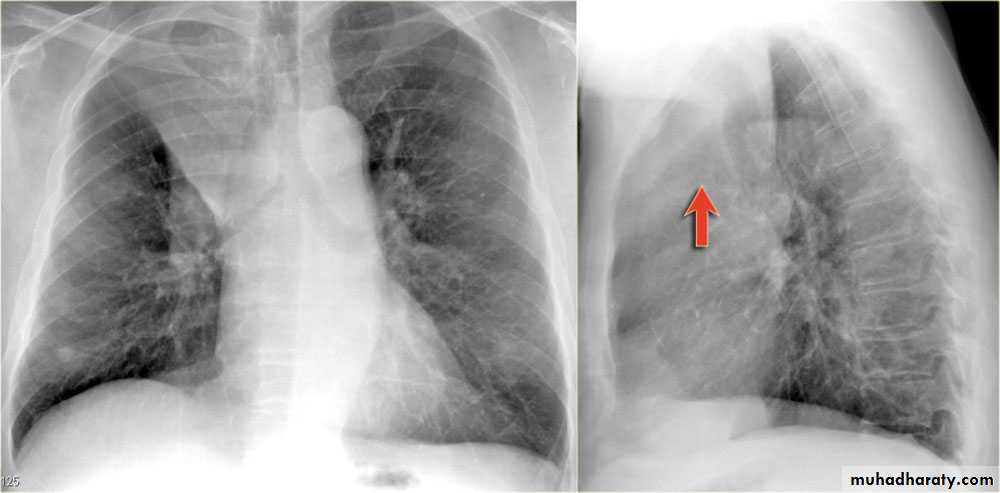

Severe dyspnea with shock